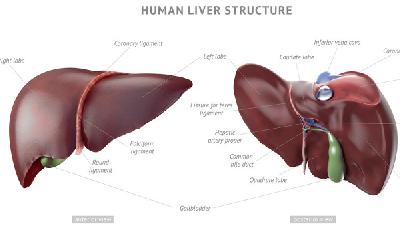

常见的肝硬化治疗药物有哪些

肝硬化是一种发病率很高的疾病,一旦患上肝硬化,如果肝硬化患者没能得到及时治疗,病情就会蔓延全身,严重危害肝硬化患者的自身健康,给肝硬化患者带来了极大的痛苦,那么常见的肝硬化治疗药物都有那些呢?下面就为大家介绍一下。1、保护肝细胞、促进肝细胞再生的药物,维生素类药物:B族维生素有阻止脂肪肝的发生、保护肝细胞的作用,临床上常用的有复合维生素B等药物。维生素C和维...